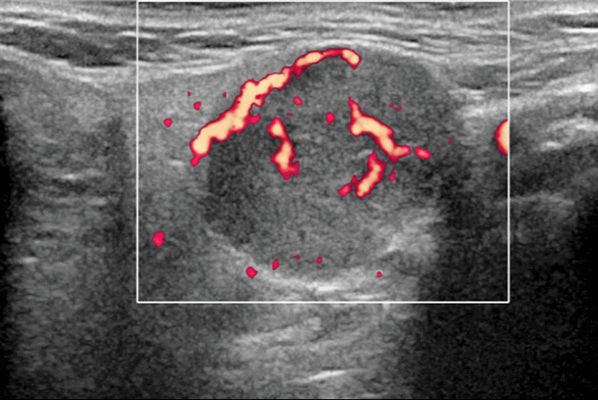

- Цветной допплер: периферические сосуды, в основном венозные.

- Спектральный допплер: низкое внутриузловое сопротивление сосудов [резистивный индекс (RI)

Цветной допплер. Периферические сосуды, в основном венозные, часто редко расположены. Спектральный допплер: низкое внутриузловое сопротивление сосудов [резистивный индекс (RI) Результаты MРТ